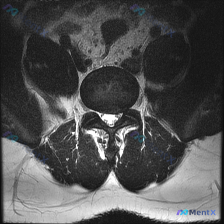

刚整理完一个挺有启发的阅片病例,分享给大家一起讨论,这个病例最值得思考的就是「临床怀疑和影像结果矛盾的时候该怎么分析」。 病例基础信息 本次分析对象为一张腰椎MRI轴位T2加权像,临床核心假设为「椎间盘病变」,问题是明确这张图像上存在的视觉异常体征。 影像阅片结果 这是腰椎下段(L4/5或L5/S1...

今天整理了一份只有单张腰椎MRI T2加权轴位片的椎间盘病变分析案例,跟大家分享一下读片和临床分析的思路。 病例影像基本信息 本次仅提供单张腰椎MRI T2加权轴位图像,具体读片发现如下: 1. 节段定位:根据椎体、椎弓根和关节突形态判断,该切面位于腰椎,最可能为L4/5或L5/S1水平 2. 椎间...